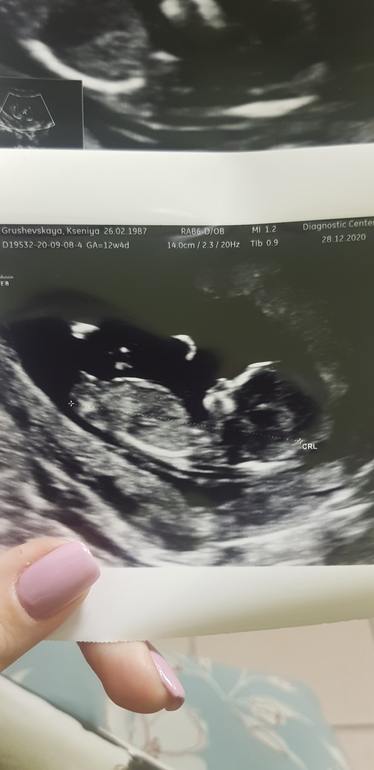

1 скрининг пройден! Погадаем кого ждём?

Результаты: УЗИ, КТГ, доплера, скринингаБыли сегодня с мужем на первом скрининговом узи.Ура!))) Все у кнопочки чудесно!КТР 6,4 смВоротниковое пространство 1,7Носик хорошо виден.Сердечко стучит 170 уд/минВесит 72 грамма! Ну прям такой упитанный человечек.Лежал(а) деловая нога на ногу 🤣👌По НИПТу мы уже знали, что нет хромоссомных болезней, поэтому только анатамия была важна. А анатомия отличная. Профиль прям красивый - в меня конечно 🤣🤗Записали видео, дали фото. Ну и конвертик дали (пол определён по результатам НИПТа, но мы не хотели сразу знать, 31 декабря будет сюрприз). Хотя вот по фото я конечно догадываюсь кого ждём))))

Как вы думаете, кто это тут такой деловой?